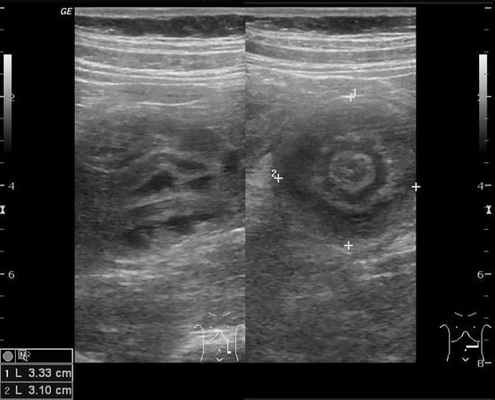

На рисунках 2 и 3 отображена ультразвуковая картина кишечной инвагинации.

Рис. 2. Симптом «мишени»

Рис. 3. Симптом «псевдопочки»

В момент УЗ-исследования врач может определить один из симптомов:

- симптом мишени (за счёт внедрения одной кишки в другую инвагинат на срезе выглядит как мишень);

- симптом "почки с завоздушенным центром".